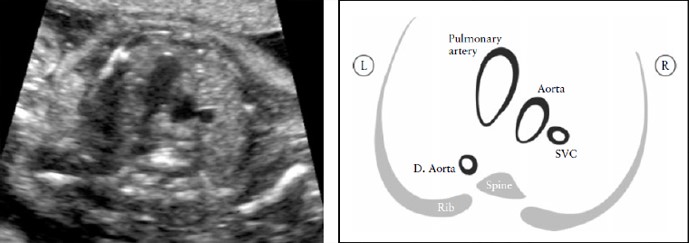

Yoo et al [64] описали проекцию трех сосудов для оценки состояния легочной артерии, восходящей аорты и верхней полой вены и определения их относительных размеров и взаимоотношения (Рисунок 7). В целом, необходимо определить количество сосудов, измерить их размер и оценить их взаиморасположение и ход. Сосуды, если смотреть слева направо, представляют собой: легочную артерию, аорту и верхнюю полую вену.

Рисунок 7. Срез через три сосуда (3V). Это срез наилучшим образом демонстрирует соотношение в верхнем средостении между легочной артерией, аортой и верхней полой веной (SVC). Очень важно оценить размер этих сосудов, их расположение и совпадение их осей. Легочная артерия слева; она наибольшая среди этих сосудов и расположена более кпереди, верхняя полая вена наименьший сосуд и расположена наиболее сзади. D. Aorta, нисходящая аорта.

Легочная артерия располагается наиболее спереди, а верхняя полая вена расположена наиболее сзади. Их относительный диаметр уменьшается слева направо: легочная артерия больше, чем аорта, но аорта больше, чем верхняя полая вена. Как правило, некоторые пороки сердца, с нормальным четырехкамерным срезом сердца (например: транспозиция магистральных артерий, тетрада Фалло и легочная атрезия с ДМЖП) скорее всего будут иметь нарушения в проекции трех сосудов. Yagel et al [67] впоследствии описали проекцию трех сосудов и трахеи, которая является более краниальным срезом.